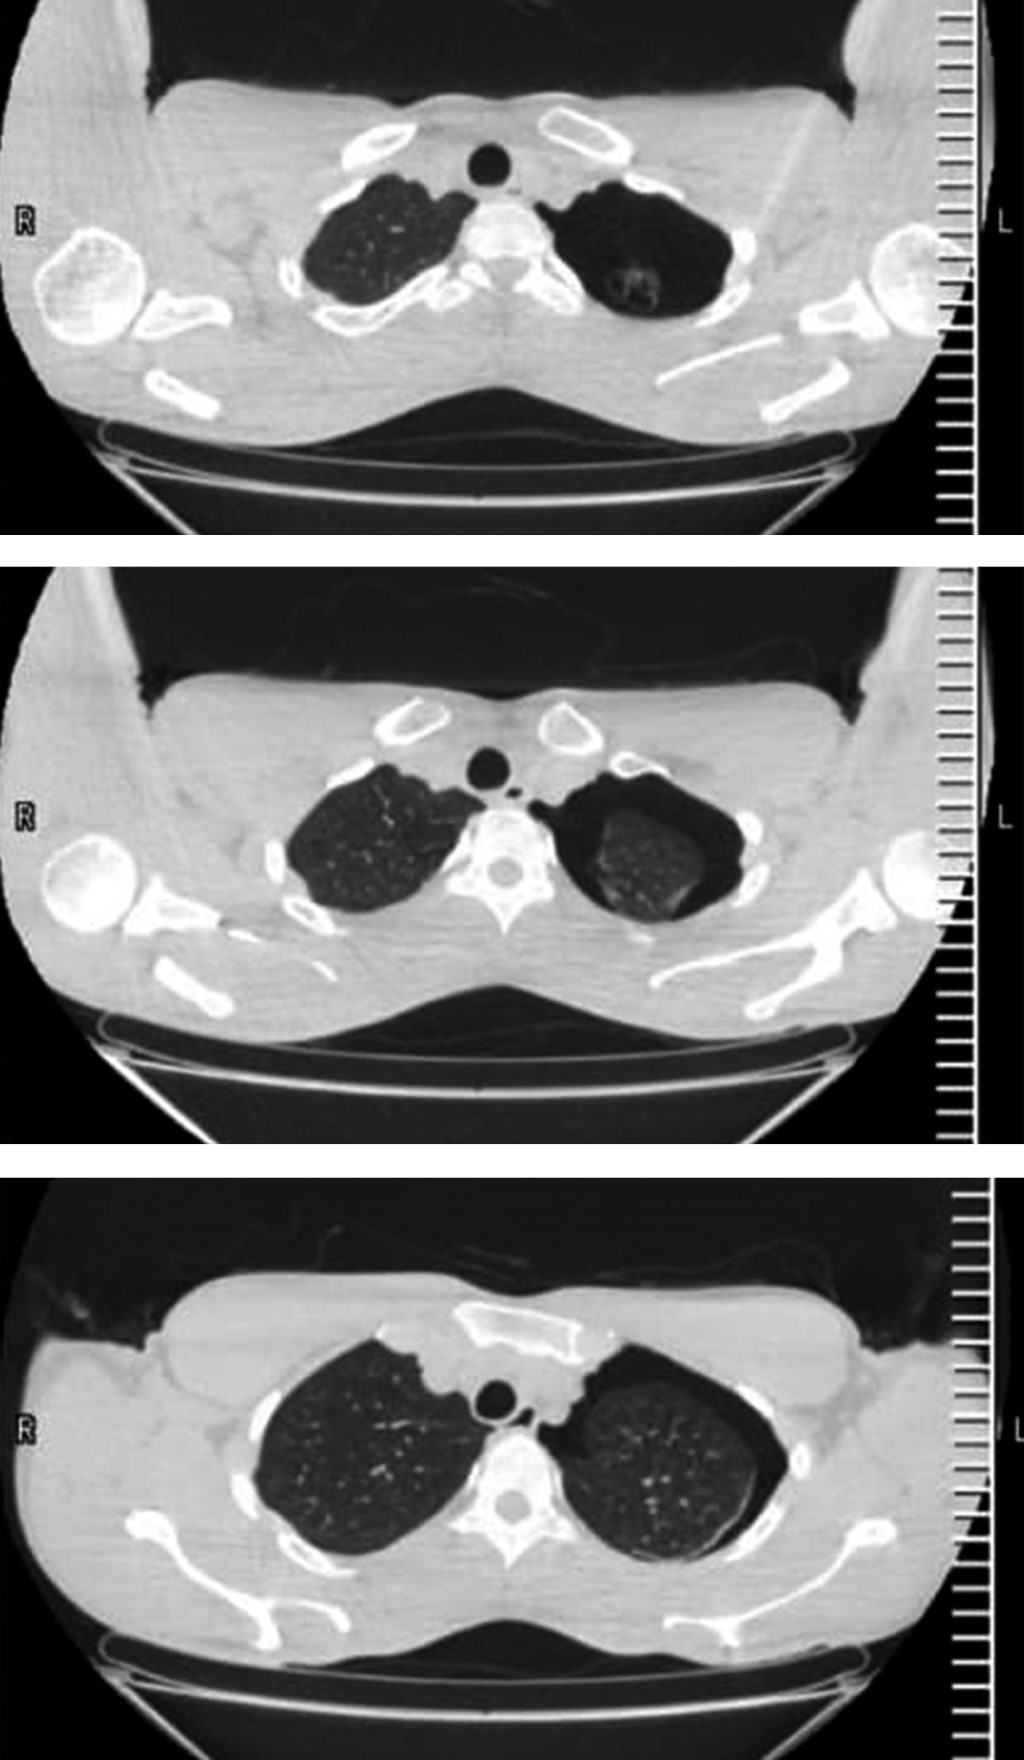

Las causas más comunes de enfisema bulloso incluyen el tabaquismo, la exposición a biomasa y la deficiencia de α-1 antitripsina. Los síntomas incluyen disnea progresiva, tos productiva, disminución de la tolerancia al ejercicio y sibilancias. Las opciones de tratamiento quirúrgico incluyen toracotomía o videotoracoscopia. Al elegir el abordaje ideal para cada paciente, se deben considerar la extensión y la ubicación de las bullas, las comorbilidades y el riesgo de recurrencia, entre otros factores. Presentamos dos casos quirúrgicos: una mujer de 45 años con antecedentes de exposición a biomasa y una bulla gigante que le causó dificultad respiratoria aguda, tratada con éxito mediante toracotomía; y un hombre de 25 años que desarrolló un neumotórax espontáneo con quistes subpleurales asociados con gran altitud, tratado mediante bullectomía videotoracoscópica.

Figura 1